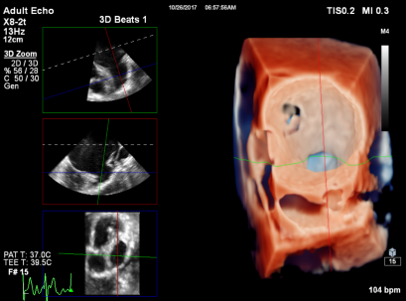

EPIQ CVxiににおける卓越した3D技術

EPIQ CVxiはEPIQ CVxにおける3D技術を踏襲。その中でもTrueVueは超音波診断装置の処理能力が向上したことにより実現した,3Dレンダリングにおける新技術である。異なる光の波長ごとにその挙動をモデル化し,より“リアリスティック”な画像をご提供します。さらに3Dボリュームデータをタッチスクリーンでタブレット式に操作できるTouchVueも搭載されており,インターベンション治療の現場で迅速な操作が求められる場合にも,必要なビューを直観的に描出できるワークフローとなっている。

TrueVueを用いた左心耳の3D画像